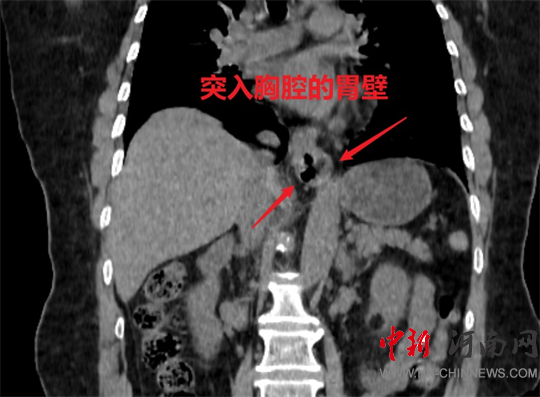

食管裂孔疝是指腹腔內(nèi)的臟器(主要是胃,也包括小腸和大網(wǎng)膜等)通過(guò)人體的膈肌食管裂孔進(jìn)入胸腔所導(dǎo)致的疾病。

食管裂孔疝患者會(huì)有燒心、反酸、噯氣、胸痛、吞咽困難等相關(guān)癥狀,以及會(huì)出現(xiàn)出血、反流性食管狹窄、疝囊嵌頓等相關(guān)并發(fā)癥;胸腔內(nèi)的臟器如心臟、肺、縱隔等可能受到疝囊的壓迫,還會(huì)產(chǎn)生氣急、心悸、咳嗽、發(fā)紺等癥狀。

這種手術(shù)方式

通過(guò)腹腔將進(jìn)入胸腔的臟器

拉入原來(lái)的位置

減少了開(kāi)胸手術(shù)的創(chuàng)傷